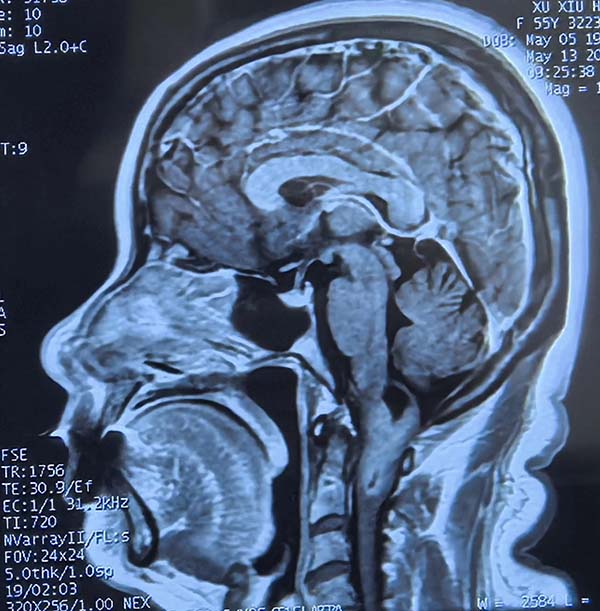

01  5月12日(ri)

5月12日(ri),一(yi)位飽受延頸交界區(qu)腫瘤折磨的(de)患者,輾轉來到(dao)北京航天總醫(yī)院神經(jing)外科(ke)。延頸交界區(qu)腫瘤位置險要,緊鄰生(sheng)命中(zhong)樞——延髓及(ji)頸髓上段,手術(shù)風險極高(gao),被喻爲(wei)神經(jing)外科(ke)的(de)“終極挑戰”。在(zai)此方(fang)寸之(zhi)地施術(shù),不啻于(yu)懸崖峭壁上的(de)精(jīng)微雕刻,稍有(yǒu)不慎便可(kě)能(néng)導(dao)緻呼吸(xi)功能(néng)永久性損傷。而術(shù)後(hou)護理(li),更昰(shi)關乎患者生(sheng)死存亡的(de)關鍵戰場(chang)。